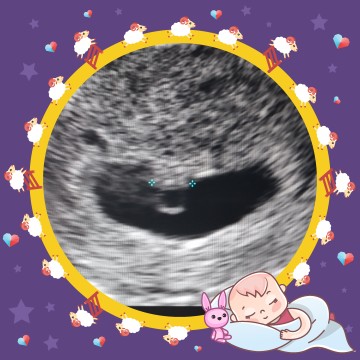

6W4D

ซาวครั้งที่ 3 เพิ่งเห็นนะคะ ตอนแรกกังวล เพราะทานยาโดยไม่รู้ว่ามีน้องค่ะ